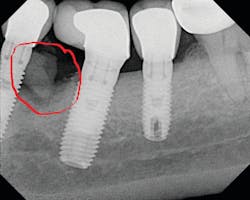

Once again, the literature is replete with case reports and case series describing soft- and hard-tissue loss due to excess dental cement left at the time of implant crown insertion.8 In one study, 90% of the implant crowns inserted with cement exhibiting inflammation and bleeding upon probing were due to cement in the peri-implant sulcus.9 Cement acts as a nidus for bacteria and induces a rapid hard-tissue loss around the dental implant fixture (figures 2 and 3).

Detecting excess cement can usually be done with a radiograph if the cement is located in the interproximal region and is radiopaque (figure 4).